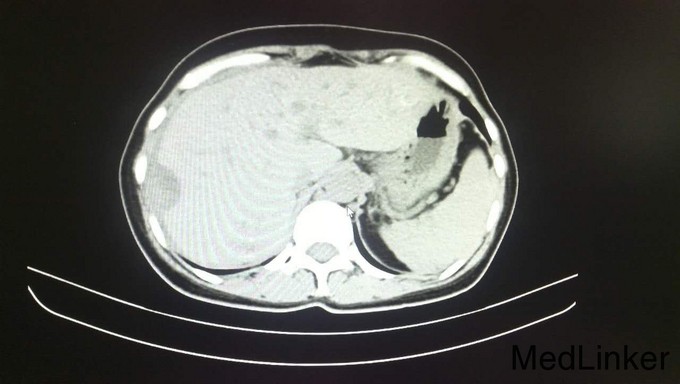

查体:腹平软,全腹部未扪及明显包块,全腹无压痛、反跳痛,右侧上中腹部可见一长约12cm的手术瘢痕,愈合良好,肝脾肋下未触及,墨菲氏征阴性,移动性浊音阴性,肠鸣音正常,无血管杂音。双肺呼吸音清,未闻及干湿性啰音,心脏听诊律齐,各瓣膜区未闻及明显病理性杂音。四肢查体无明显异常。 辅查:术后病理示:右半结肠中分化腺癌,部分为粘液腺癌,浸润肠壁全层,并侵犯神经组织,胰腺旁淋巴结见癌组织浸润并侵犯神经组织。2015年4月全身PET/CT检查示:右半结肠吻合口未见占位,纵膈1L组、肝门、腹膜后、右侧结肠旁沟淋巴结转移瘤,肝内转移瘤,胰头下方软组织转移瘤,双肺多发小结节,不排除转移瘤。2015年6月复查CEA:1353ng/mL,CA199:9674u/mL(较前明显升高)。其余重要影像学检查如下图所示: